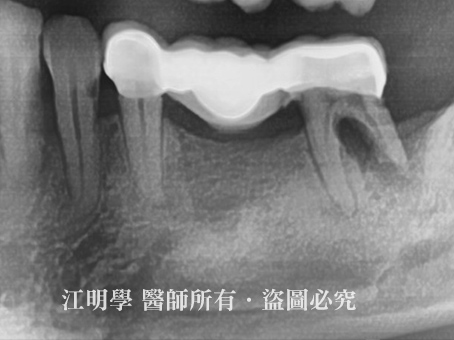

治療前X光